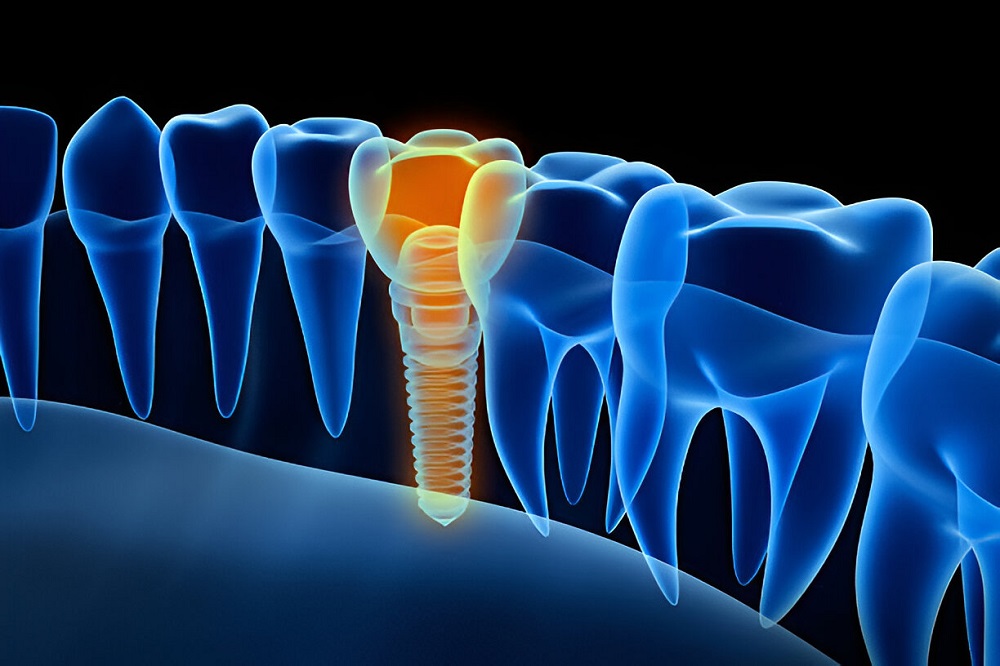

One popular surgical implant dentistry alternative is implant dentistry, which supports prosthetic teeth, including crowns, bridges, and dentures. Implant placement may involve a few procedures and several months of healing, but after the implant heals, it can be used as a natural tooth and, with the right maintenance, can last a lifetime.

A dental surgeon places artificial devices called implants dentistry into the mandible. If a person has lost one or more teeth, they may need implants.

Through dental implant surgery, damaged or missing teeth are replaced with artificial teeth that function and look a lot like natural ones, and tooth roots are replaced with metal, screw-like posts. When there are insufficient natural tooth roots to support dentures or bridgework, dental replacements, this procedure may potentially be a possibility.

The major advantage of implants is that they provide solid support for the new teeth, which requires the bone to heal tightly around the implant. However, because bone healing takes time, this process can take several months.